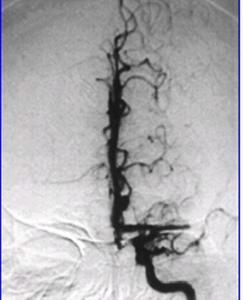

(三)非創傷性血管檢查雙功超聲(duplexsonography)可用於評估顱外段頸動脈病變及狹窄程度。經顱都卜勒(transcranialDoppler,TCD)可檢測腦底大動脈流速,發現大腦中動脈主幹、椎動脈遠端段和基底動脈狹窄或阻斷,可評估側枝循環情況。新近發展的雙焦探頭TCD儀、雙通道或四通道TCD儀可用於檢測無症狀栓子和椎測栓子的心源性或動脈源性。磁共振血管造影(MRIangiography)可用於檢查顱外和顱內供腦大動脈的病變。

(四)動脈造影選擇性腦動脈造影和數減動脈造影(DSA)適用於超聲檢查發現嚴重狹窄的頸內動脈而考慮進行頸動脈內膜切除術的病人或臨床表現不尋常而懷疑動脈分層或動脈炎者。這是一種創傷性檢查,2%~12%的受檢者可能並發動脈分層或栓塞性中風。